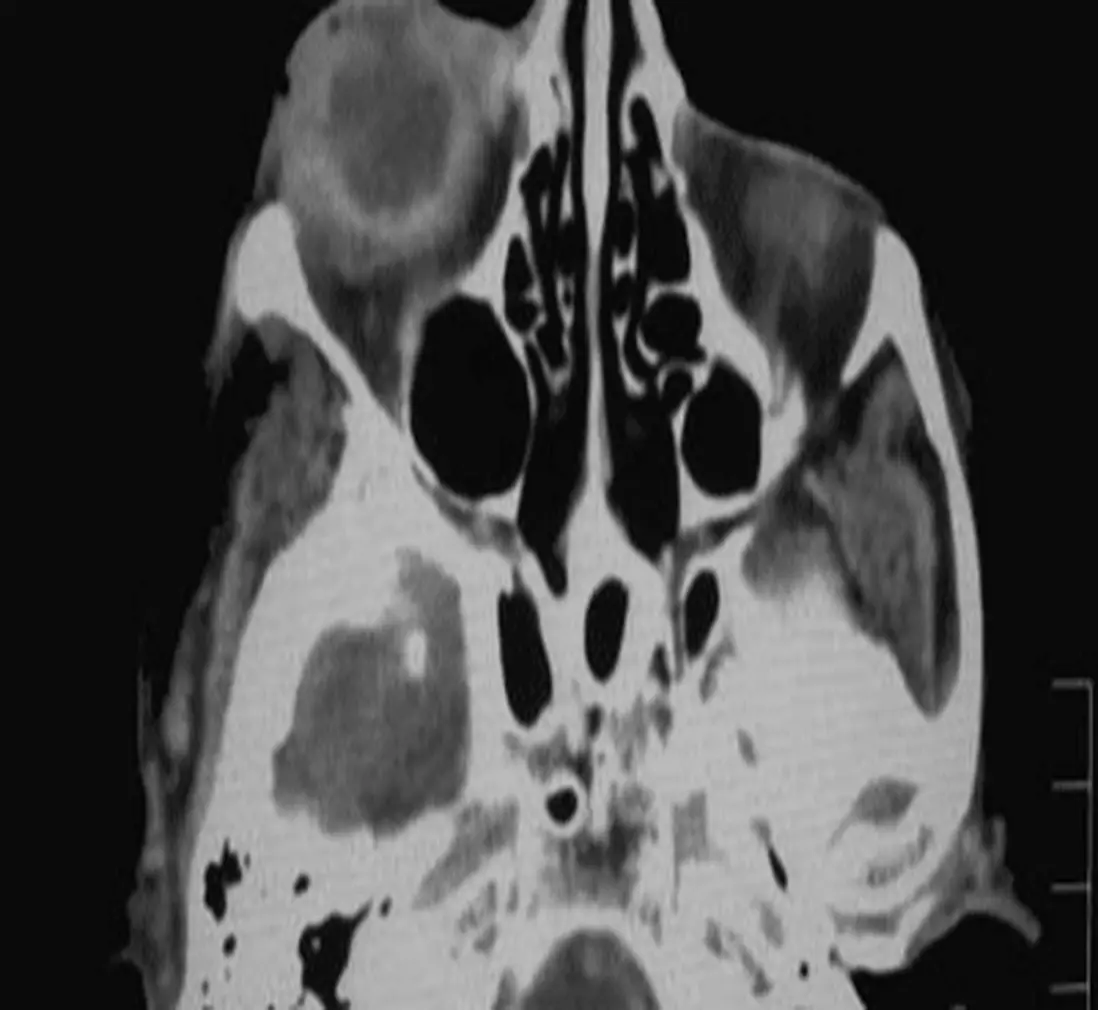

To deliver precise eye diagnosis within seconds, the company acknowledged that its AI eye screening model needed to be trained rigorously and enriched with a combination of accurately annotated data – such as retinal photography, CT scan images, and medical reports. Thus, the data annotation process is essential to perform eye screening at scale to achieve the company's mission to improve people’s vision.

Understanding the variety of patient data needed to diagnose eye conditions, the company realized the complexity and challenge to train the AI eye screening model. One of the challenges is finding a solution that is fully compatible with the different data types, especially for specific ones such as CT scan data. The company found it difficult to manage when they needed to host the labeling process with different tools to annotate different data, as each tool has a different flow some are more complex than the other, and the whole process became inefficient.

Another challenge is the need to speed up the labeling process, as to enrich the AI model, they need to only train rigorously in terms of rounded data types, but also terms of voluminous amount – while ensuring precise quality. When the team annotates retinal and CT scan images, these images need to be cut down into manageable sizes to prevent being lost and missing details. Therefore, the total amount of training datasets multiplied significantly, and the annotation process and ensuring quality is certainly time-consuming.